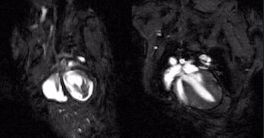

UC San Diego scientists have uncovered a transformative new understanding of heart attacks. The research, which connects the heart, brain and nervous and immune systems, shows that blocking key signals can lead to new treatments for heart attacks and minimize their resulting damage.